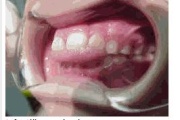

Lutipudelikaariese kahjustused

Lutipudelikaaries